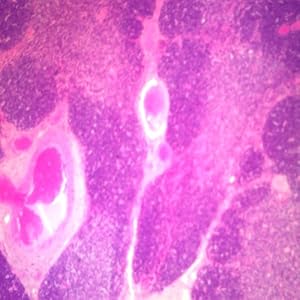

Human Thymus Microscope Slide, sec.